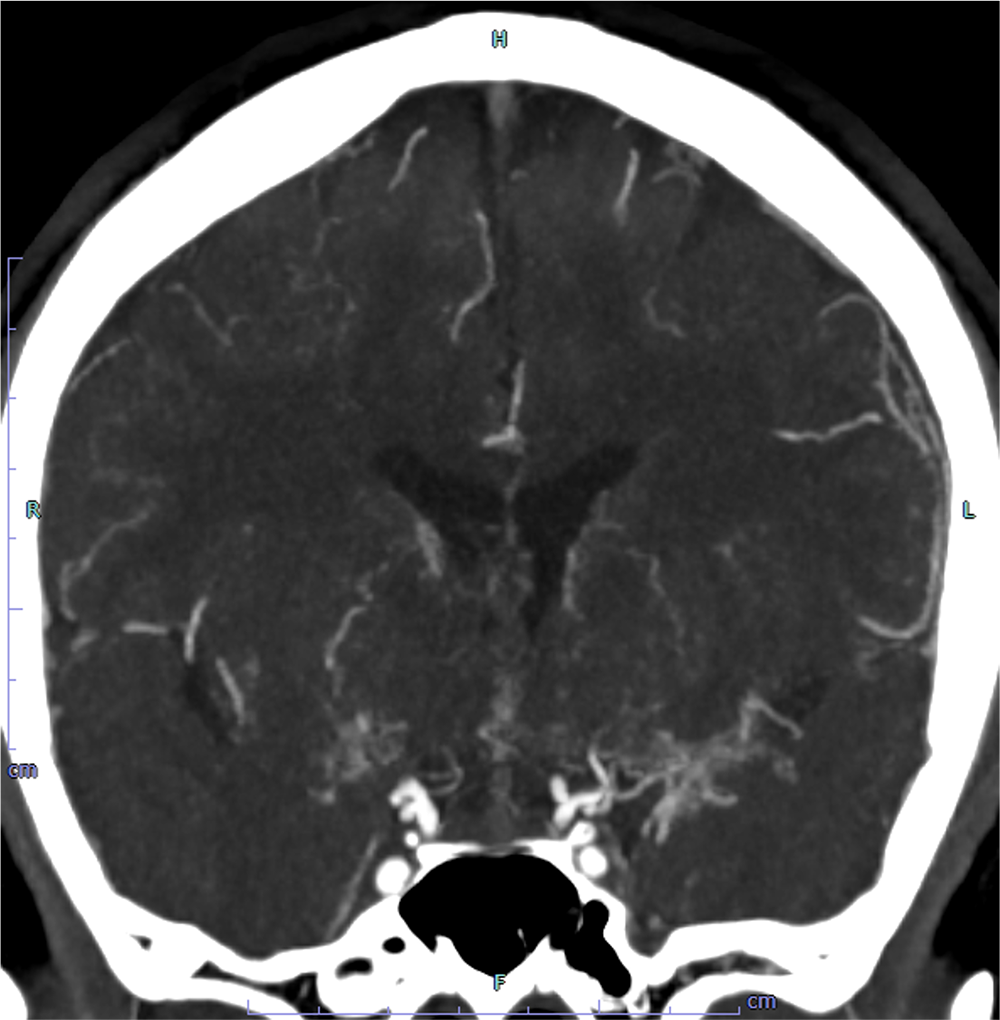

14歳ごろから手足の痺れやめまいなどを自覚しており、兄弟のもやもや病による脳卒中を契機にMRI撮像され、もやもや病と診断された。CTAで両側内頸動脈は閉塞しており、周囲に微細な増生血管をみとめた。前大脳動脈や中大脳動脈は狭窄しており、両側後大脳動脈に拡張を認めた。脳血流SPECTで左前頭葉、側頭葉に血流低下を認め、間接的血行再建術が施行された。

もやもや病における新生血管(もやもや血管)は血管径が細く、通常の撮影では明瞭な描出が難しいことがある。100kVの低管電圧撮影を用いることでもやもや血管の微細なネットワークを鮮明に描出し、病状評価や治療計画立案に役立てている。

CT技術や撮像プロトコル設定について